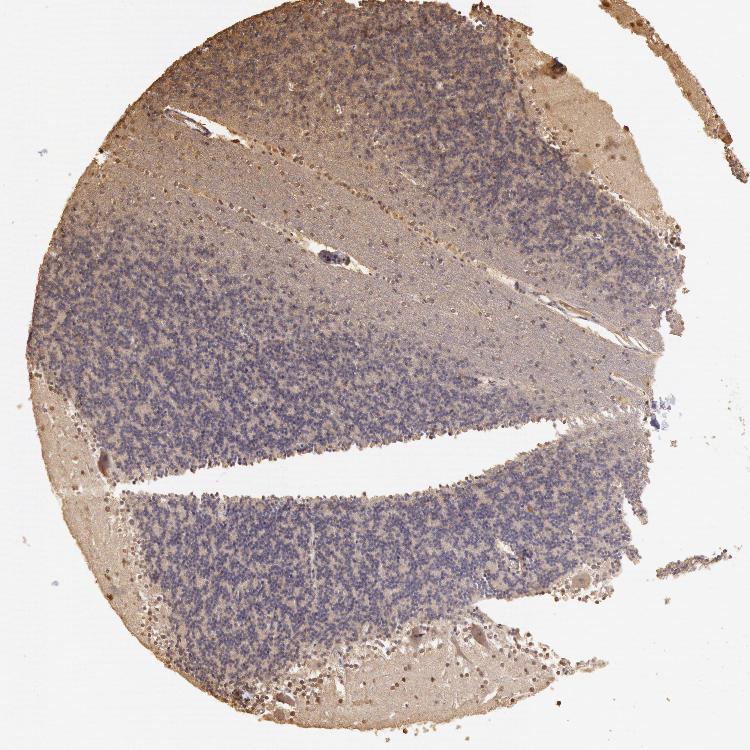

CEREBELLUM - Antibody stainingi

Antibody staining in the annotated cell types in the current human tissue is reported as not detected, low, medium, or high, based on conventional immunohistochemistry profiling in selected tissues. This score is based on the combination of the staining intensity and fraction of stained cells.

Each image is clickable and will lead to virtual microscopy that enables deeper exploration of all samples and also displays staining intensity scores, fraction scores and subcellular localization as well as patient and tissue information for each sample.

Antibody HPA001401Antibody CAB008670

Bergmann glia - cytoplasm/membrane -Not detected

Bergmann glia - nucleus -High

GLUC cells - cytoplasm/membrane -Not detected

GLUC cells - nucleus -Not detected

Purkinje cells Low-

Purkinje cells - cytoplasm/membrane -Low

Purkinje cells - dendrites -Not detected

Purkinje cells - nucleus -Not detected

Cells in granular layer Not detected-

Cells in molecular layer Medium-

Granular cells - cytoplasm/membrane -Not detected

Granular cells - nucleus -Low

Molecular layer - neuropil -Not detected

Molecular layer cells - cytoplasm/membrane -Not detected

Molecular layer cells - nucleus -High

Processes in granular layer -Not detected

Processes in molecular layer -Not detected

Processes in white matter -Not detected

Synaptic glomeruli - capsule -Not detected

Synaptic glomeruli - core -Not detected

White matter cells - cytoplasm/membrane -Not detected

White matter cells - nucleus -High